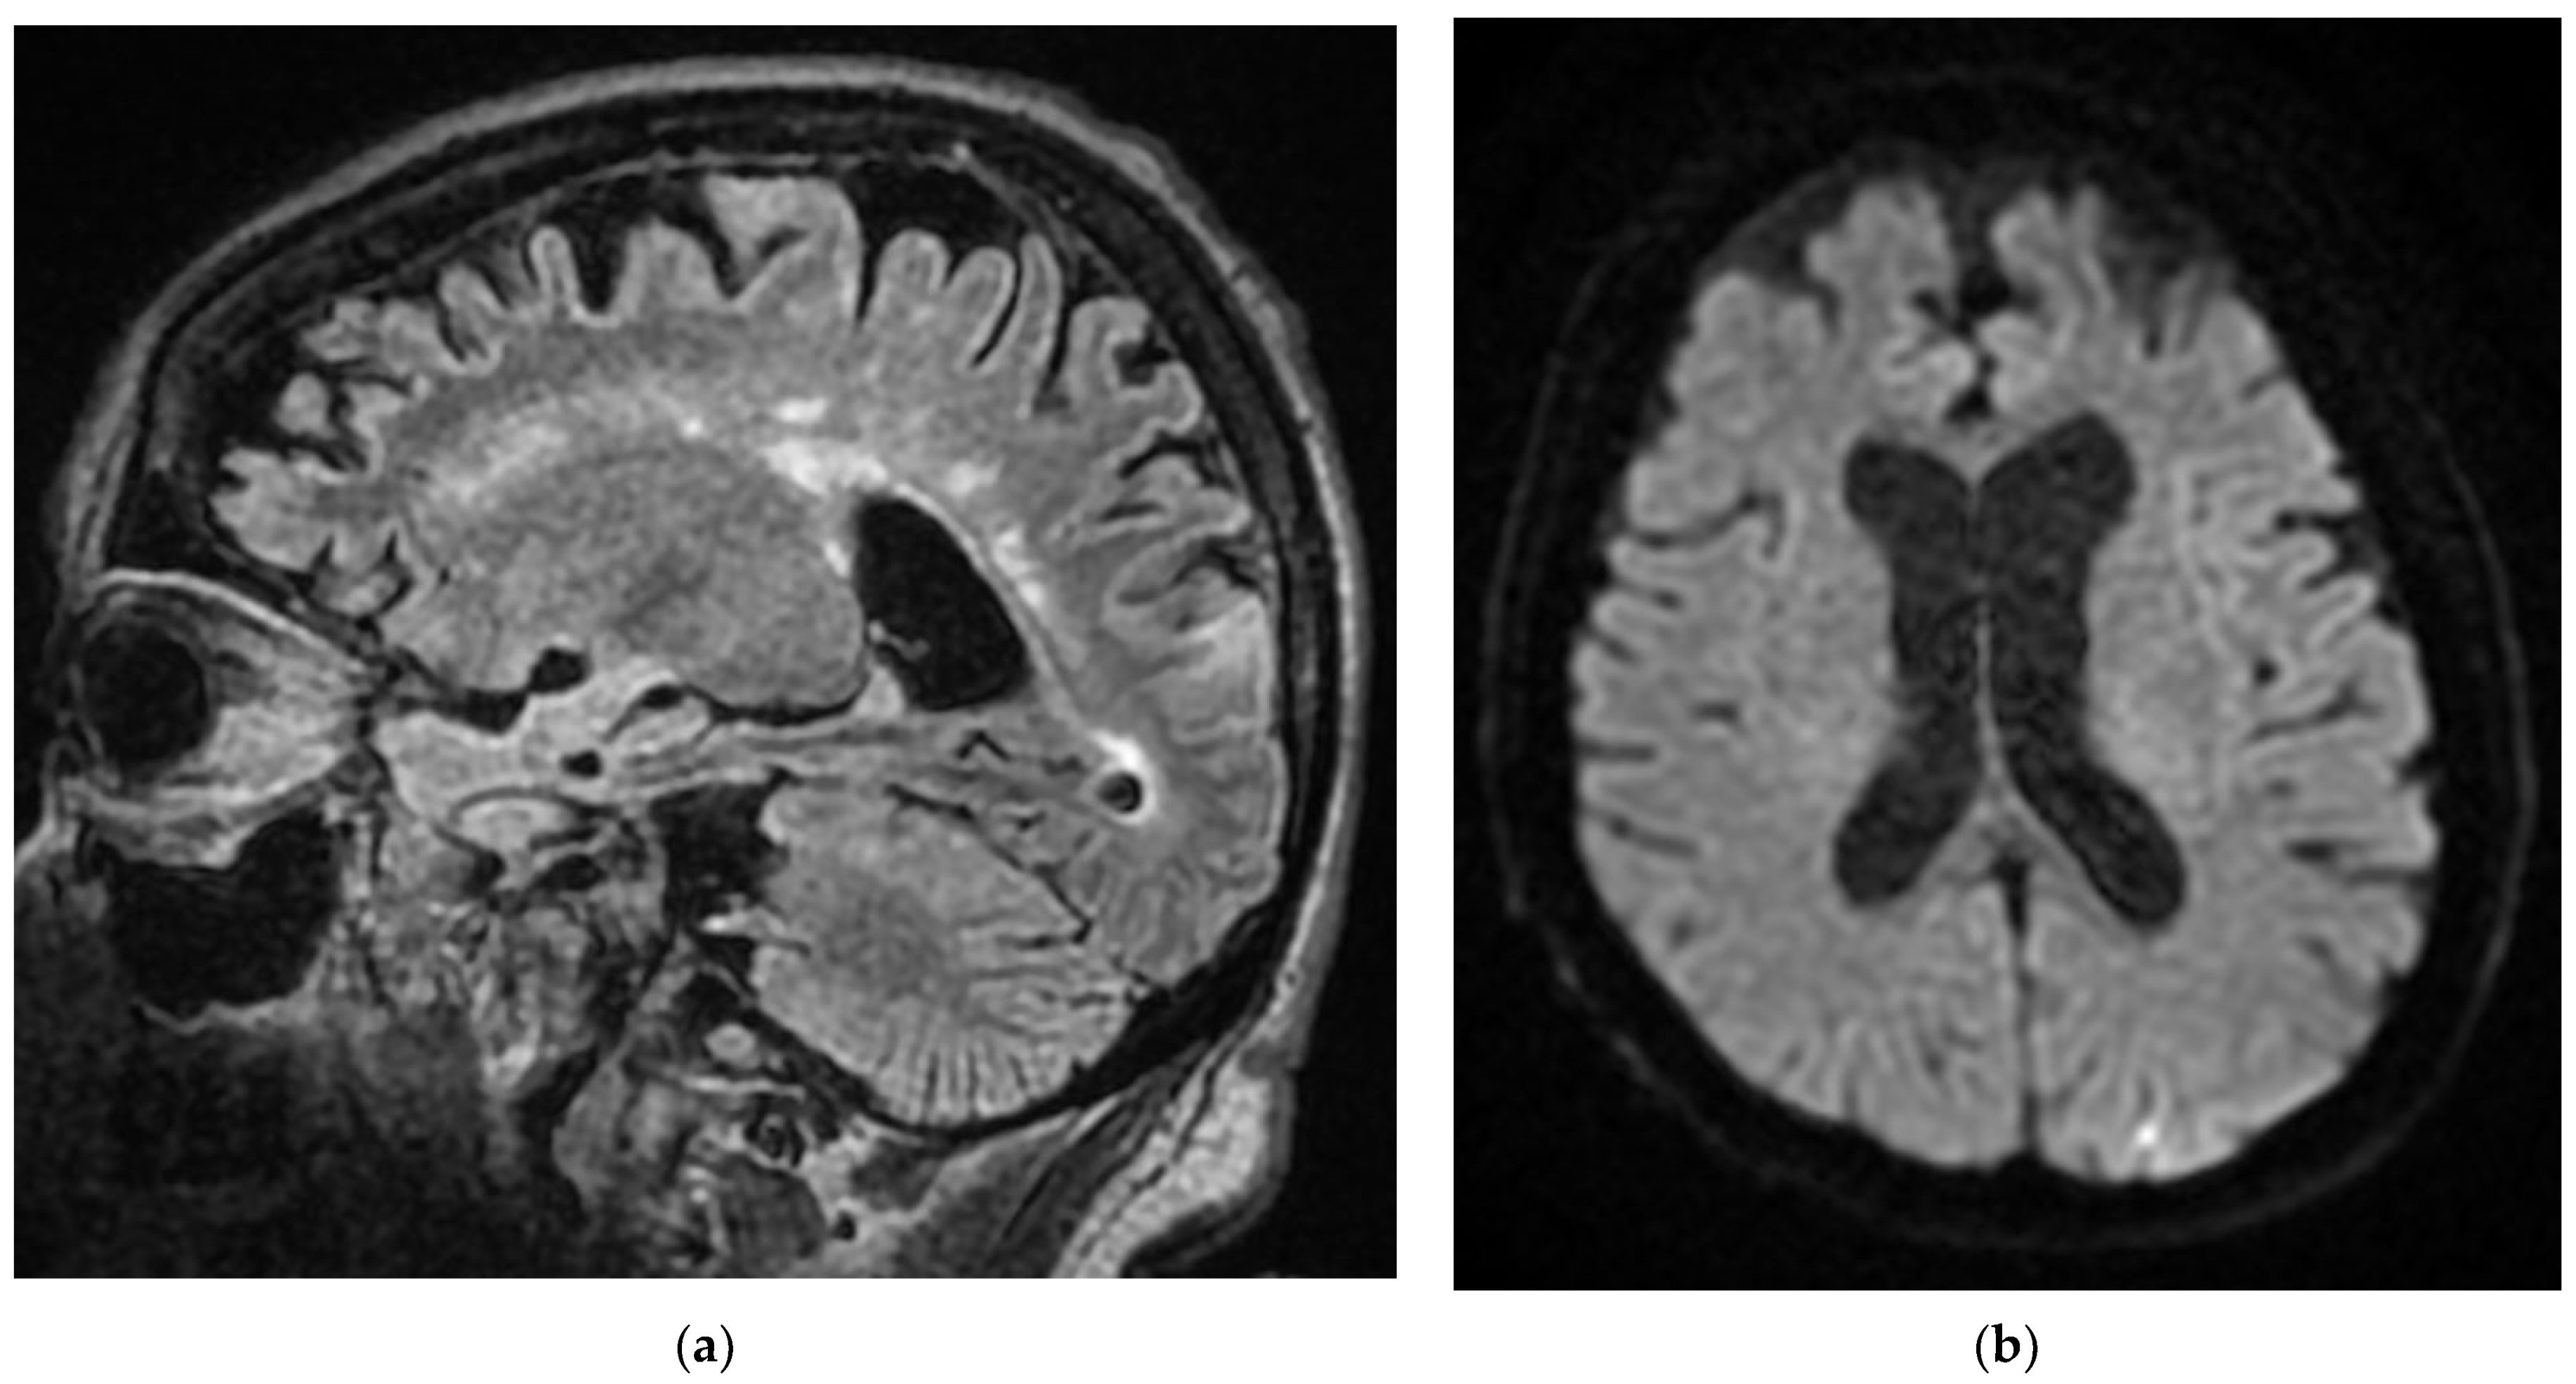

A recently infected 72-year-old elderly patient with a severe form of COVID-19 was transferred from the Cardiology department with acute fibro flutter, and a recent brain CT (admission from Infectious Diseases Hospital) showed left ischemic PCA stroke appearance, with a brain MRI describing a left ischemic ACP stroke that transformed into hemorrhagic stroke, present during acute COVID-19 infection and post-hospitalization at home with bilateral lower limb plegic motor deficit.

Neurological objective assessment on admission showed the patient to be conscious, partially cooperative, and partially temporospatially oriented, with a right-upper-limb motor deficit, flaccid paraplegia, abolished osteotendinous reflexes in the lower limbs, and no tactile surface sensitivity disorders. During hospitalization, she underwent native and contrast-enhanced chest CT scanning, which showed alveolo-interstitial changes suggestive of post-COVID-19 status, lumbar puncture (CSF macro- and microscopically normal appearance), and a thoracolumbar spine MRI showing a left minor split disc L5-S1 with a subligamentary nonmigrated pulposus nuclear fragment. Biological tests revealed liver cytolysis, hypokalemia, and corrected hyperglycemia. During hospitalization, she was treated with statin, antiplatelet, and hydration infusion solutions, with unfavorable evolution. The patient suffered cardio-respiratory arrest (Figure 10, Figure 11, Figure 12, Figure 13 and Figure 14).

Figure 14. After 11 days from the first pulmonary CT, the cranio-cerebral MRI in the Case 10 patient showed foreshadowing of intense T2 signal (a), with deposits of predominantly peripheral methemoglobin (b), deficient restriction of diffusion (c,d) and gyriform gadolinium I (e), developed in the cortical–subcortical–occipital left median side with extension in the thalamic nucleus on the same part. In conclusion, infarction hemorrhagically transformed into superficial and profound territories of the left posterior cerebral artery.